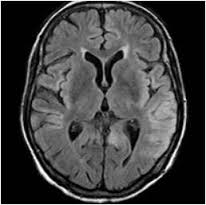

代表的な臓器は、脳、眼、心臓、大血管、腎臓です。

それが動脈硬化。